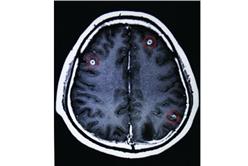

吃豬血!男子大腦生了19條寄生蟲

大陸廣西有一名男子,發覺自己經常頭暈無力,看不清東西...